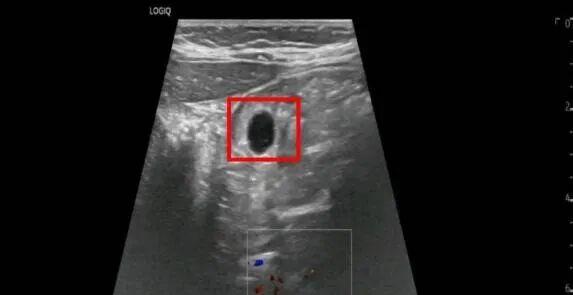

据家长描述,“水宝宝”在误服时仅有黄豆大小,可其遇水膨胀的特性让情况变得十分紧急。儿科医生王福建接诊后,第一时间联系B超室进行检查,B超室医生苏珊迅速到位,即刻为患儿开展胃肠超声检查。结果显示,仅在误服1小时后,水宝宝已在胃内膨胀至1.2x1.0cm,大小堪比玻璃球。若继续膨胀,其直径很可能超过孩子食管宽度,不仅无法通过胃镜取出,还易造成胃肠梗阻,到时候只能开刀手术!情况刻不容缓!